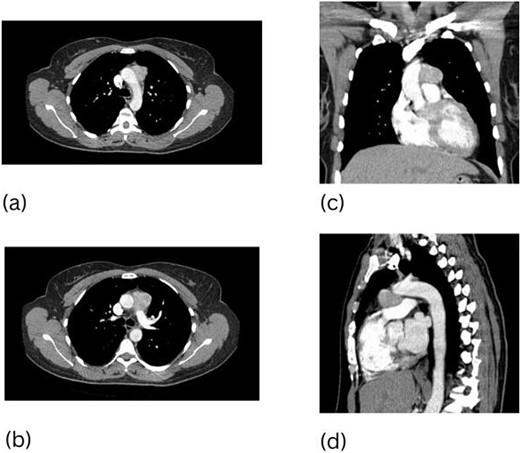

A 48-year-old woman presented with a mediastinal mass that was found during work up of an enlarging right neck mass. The neck mass was confirmed to be a carotid body paraganglioma and thus resected. After full recovery from her index surgery, a CT scan of her chest was done revealing a 3.7 cm mediastinal mass in the AP window with hypermetabolic activity seen on subsequent CT-PET (Fig. 2). Resection of this mass required a median sternotomy and CPB due to the significant number of vascular tributaries and dense adhesions between the mass and the aorta.

This paraganglioma circumscribed the entire aortic arch. The mass was sharply dissected off the aorta and then off the pulmonary artery, completing the resection. The paraganglioma measured 3.7 × 3.5 × 2.0 cm with immunoreactivity to chromogranin, synaptophysin, and S100. The patient required 57 min on CPB. The postoperative course was uneventful with full recovery. Surveillance imaging done 7 years after resection did not show recurrence.